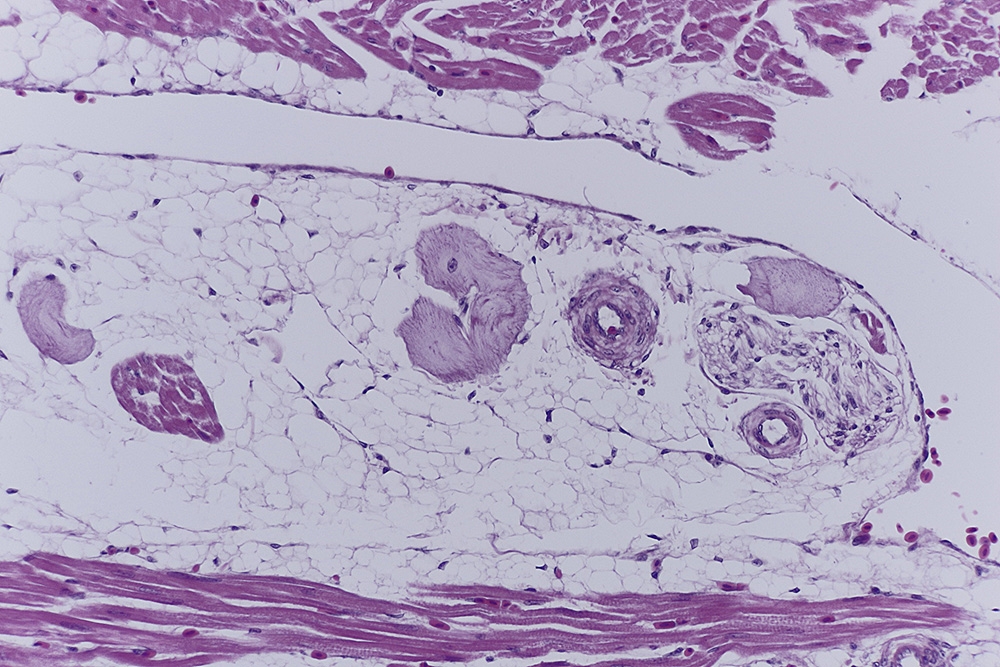

Abb.3

Abb.4

meine Glückwünsche zu den tollen Schnitten! Mir fällt vor allem beim letzten Bild und dem Querschnitt  bei 9 Uhr das ,,Hüllgewebe" auf mit seinen schmalen länglichen Zellkernen.Möchtest Du vielleicht etwas dazu sagen?

Was mich aber auch interessierte war wie das in Kunststoffschnitten aussieht, und wie der Strukturerhalt ist. Also habe ich in Technovit 7100 umgebettet und bei 1,5µ geschnitten.

Ich denke, dass es sich bei den umliegenden Strukturen um die Zellkerne von Bindegewebszellen handelt.

Was mir aber sehr gefällt, ist der schöne Strukturerhalt nach dem Umbetten.